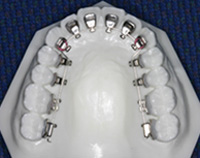

内側矯正治療

歯列の内側に装置を付けて行う治療です。

外側からは見えません。